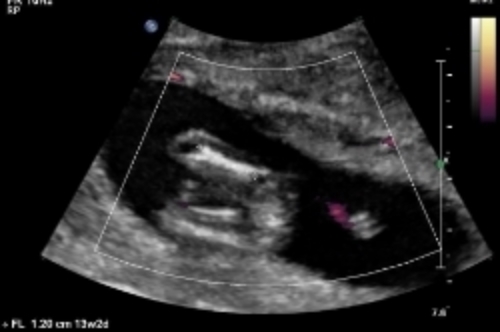

Here are some u/s pics from my friend at 13 weeks. Any nub guesses?

Attachment 24161